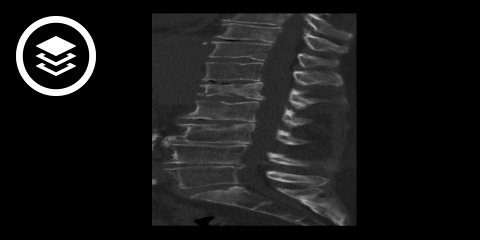

CT-Fallbeispiel

- Bildquelle DICOM-Viewer: Datensatz freundlicherweise zur Verfügung gestellt durch die Klinik für diagnostische und interventionelle Radiologie, St. Vinzenz Hospital Köln